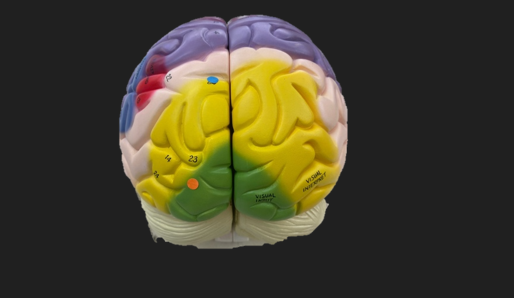

orange dot

frontal lobe

blue dot

longitudinal fissure

dark green dot

precentral gyrus

pink dot

postcentral gyrus

yellow dot

central sulcus

white dot

parietal lobe

light green dot

Broca’s Area

red dot

Wernicke’s Area

orange dot

occipital lobe

blue dot

parieto-occipital sulcus